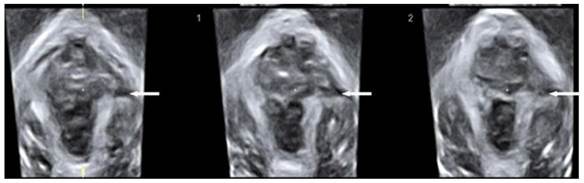

The diagnosis of puborectalis avulsion was made on tomographic ultrasound imaging (TUI) on the maximum pelvic floor contraction. A set of 8 parallel tomographic slices was obtained in the axial plane at intervals of 2.5 mm from 5.0 mm caudal to 12.5 mm cephalad of the plane of minimal hiatal dimensions. The puborectalis avulsion was diagnosed when there was loss of continuity between muscle and pelvic sidewall at least on one slice. Avulsion includes full avulsion and partial avulsion. Full avulsion is determined if the loss of continuity between muscle and pelvic sidewall is seen on all the three central slices; at the plane of minimal hiatal dimensions and two slices above it [18]. Partial avulsion is diagnosed when loss of continuity between muscle and pelvic sidewall is seen in less than the three central slices of TUI or in other planes than these slices.

Figure 3

Tomographic ultrasound imaging showing left-sided avulsion of the pubrectalis (arrows pointed).

The levator hiatal dimensions were significantly larger in the postpartum female than that in normal nulliparas, with an oval or circle shape. On TUI, avulsion of the puborectalis muscle was detected in eight cases among those delivered vaginally on maximum pelvic floor contraction (Fig. 3), including 4 unilateral avulsion (2 cases of full avulsion and 2 of partial avulsion) and 4 bilateral avulsion (1 case of bilateral full avulsion and 1 case of left-sided full avulsion and right-sided partial avulsion, and 2 cases of right-sided full avulsion and left-sided partial avulsion). No such defects were observed in Cesarean section group. Pelvic organ prolapse was detected on maximum Valsalva. Twelve cases displayed cystocele including 10 from Vaginal delivery group and two from Cesarean section group (Fig. 4). In the axial plane, the arrangement of urethra, vagina and rectum changed, and bladder was also detected in levator hiatus.